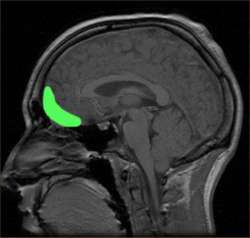

В основе отличия психопатов от нормальных людей стоит, как считают учёные, дисфункция мозга на нейробиологическом уровне, в частности, орбитофронтальной коры, и как следствие невозможность переживать "сложные" эмоции, такие как: стыд, радость, чувства раскаяния и привязанности, и как следствие эгоцентричность, лживость и поверхностность эмоциональных реакций. В основе восприятия психопата лежит мир, по-настоящему не содержащий других людей, ибо психопату недоступно их "человеческое" восприятие, связанное с эмпатией - способностью чувствовать чужие эмоции, это мир зацикленный вокруг самого психопата, стало быть всё что он делает с этими людьми легко и просто оправдывается им самим как само собой разумеющееся.Перед нами типичное лицо представителя данной патологии. В связи с неспособностью испытывать реальные глубокие эмоции такие люди часто ходят под маской за которой они пытаются скрыть свои реальные эмоции. Реальные эмоции психопатов следуют из их личностных особенностей: высокий уровень эгоцентризма, и как следствие надменность, отвращение, ну и конечно сама фактическая невовлечённость в происходящее.Скрыть свои эмоции не так то просто, взять хотя бы улыбку. Во время естественной улыбки у человека работают скуловые мышцы и нижняя часть круговой мышцы лица. При фальшивой улыбке напрягаются лишь скуловые мышцы, от того её и называют в народе "натянутой" - рот не принимает полностью правильную форму, а лишь поднимаются уголки рта, кроме того скулы смещаются чуть-чуть вверх, это не компенсирует бездействие других скелетных мышц и создаёт, со временем, характерные морщины. При искренней улыбке сокращаются мышцы над веками, брови слегка опускаются, щеки приподнимаются. При фальшивой, характерной для надменных людей, особенно заметное несоответствие линии бровей линии глазной щели. Видна общая лёгкая асимметрия лица, связанная с противоречивостью реальных эмоций и осознанных мышечных команд.Делайте выводы, господа.